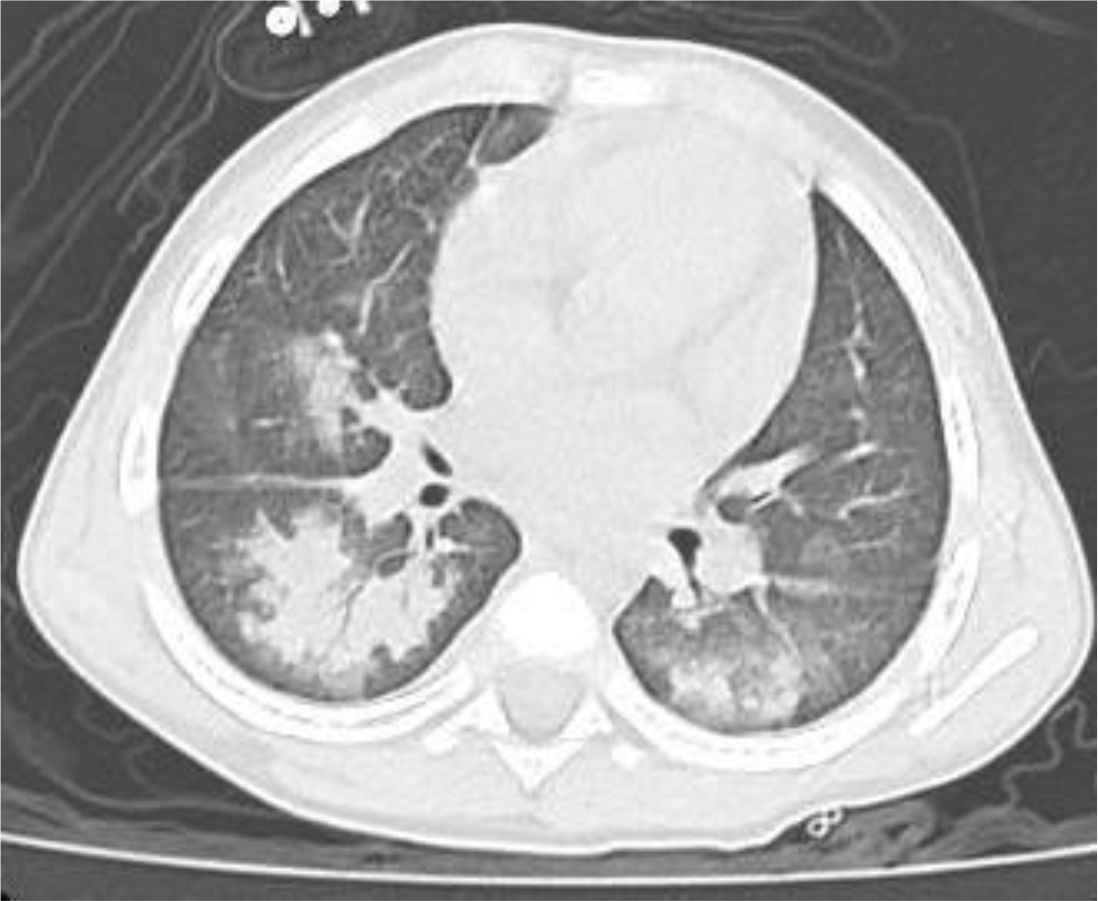

A 4 year-old male was diagnosed with HbE/Beta-thalassemia at age 2 years, and had received monthly red blood cell transfusions since. He was found to have a fully matched sibling and was scheduled for HSCT. At pre-transplant evaluation he was found to have mild hemophilia A, with no history of bleeding, and borderline low factor VIII levels discovered because of prolonged PTT at routine pre-anesthesia workup. His baseline FVIII was in the 10-20% range. He had received FVIII supplementation with PTT normalization and 28% FVIII levels. HSCT preparation consisted of fludarabine total dose 200 mg/m2, and dexamethasone total dose 125 mg/m2 on days -40 to -36, fludarabine total dose 180 mg/m2 on days -11 to -6, busulfan oral total dose 14 mg/kg from day -9 to -6, cyclophosphamide total dose 200 mg/kg from day -5 to -2. The graft source was G-CSF-primed marrow, and rejection/graft vs. host disease prophylaxis consisted of cyclosporin A and short course methotrexate. Neutrophil engraftment occurred on day +19. On day 21st post-BMT, while platelets were 18.000/µL and had received the last platelet transfusion 3 days before, he developed dry cough, respiratory distress, and hypoxemia, followed one day later by hemoptysis. He underwent a lung CT scan and found to have interstitial lung disease with areas of ground glass bilaterally, mainly in the lower lobes (Figures 1, 2). FVIII was 28%. He was diagnosed with DAH and was treated with additional FVIII concentrate (Advate), blow-by oxygen supplementation, red blood cells transfusion, platelet transfusion, methylprednisolone, tranexamic acid, and antioxidants (vitamin C and E). A chest CT repeated the following day should no hemorrhage progression and partial reabsorption of the bleeding (Figure 3). Methylprednisolone therapy was discontinued. The child had a complete clinical and radiological resolution in 6 days. (Figure 4). He had good engraftment and otherwise uneventful post-transplant course with a 4-month follow-up at the time of this report (Table 1).

CT scan of a human chest showing the lungs. The lungs appear with areas of varied density, suggesting possible abnormalities. The spine and ribs are visible in a whitish shade.

Figure 2. CT scan at the diagnosis time.